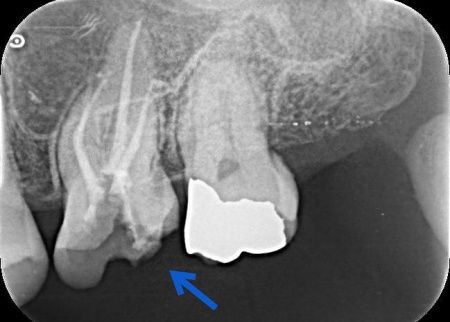

| 行ったご提案・治療内容 | 歯性上顎洞炎を改善するためには、原因となっている歯根内部の細菌をできるだけ除去する必要があります。 また、患者様は「できるだけ歯を残して治したい」と希望されていたことから、精密根管治療を提案しました。 精密根管治療ではマイクロスコープ(歯科用高倍率顕微鏡)を使用し、肉眼では確認が難しい部分を拡大しながら治療を行います。これにより、複雑な根管内部や細かな感染部位まで確認できるため、より精密な処置が可能です。 一方で、根管の形態や感染の程度によっては治療が複数回に及ぶ場合があること、また根管治療を行っても上顎洞炎の改善がみられない場合には、外科的処置や抜歯を検討する必要があることもお伝えしています。 患者様には以上の内容をしっかりとご理解いただいたうえで、治療に同意いただきました。 まずは、左上奥歯に装着されていた既存の詰め物を取り外し、根管内部を確認します。 根管内部の洗浄と消毒が完了したら、根管の内部を密封する処置を行います。 最後にレントゲン撮影を行い、根管がしっかりと封鎖されていることを確認して、治療を終了しています。 |

治療中